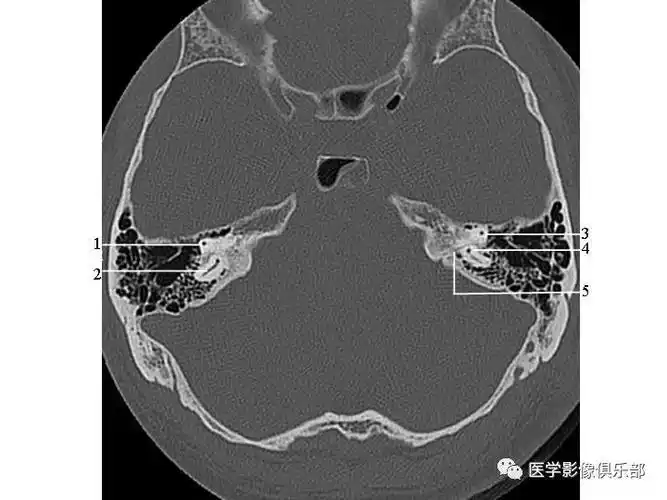

颞骨正常ct解剖附图

颞骨正常ct解剖

读书笔记:颞骨薄层ct读片心得